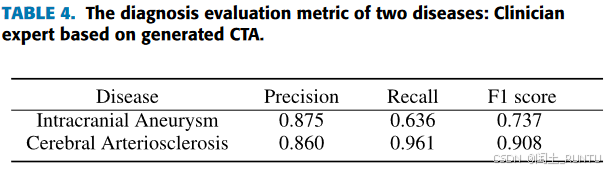

3. 诊断评估

两名放射医师根据真实CTA影像诊断颅内动脉瘤、脑动脉硬化和动脉夹层,并将其作为金标准。

为公平起见,由另外两名高级放射医师,排除100例生成CTA中质量较差的10%的数据,对剩余数据进行诊断,统计了颅内动脉瘤和脑动脉硬化两种疾病的诊断结果,如下图所示:

PS:文中并未提及各疾病类别的样本数量。